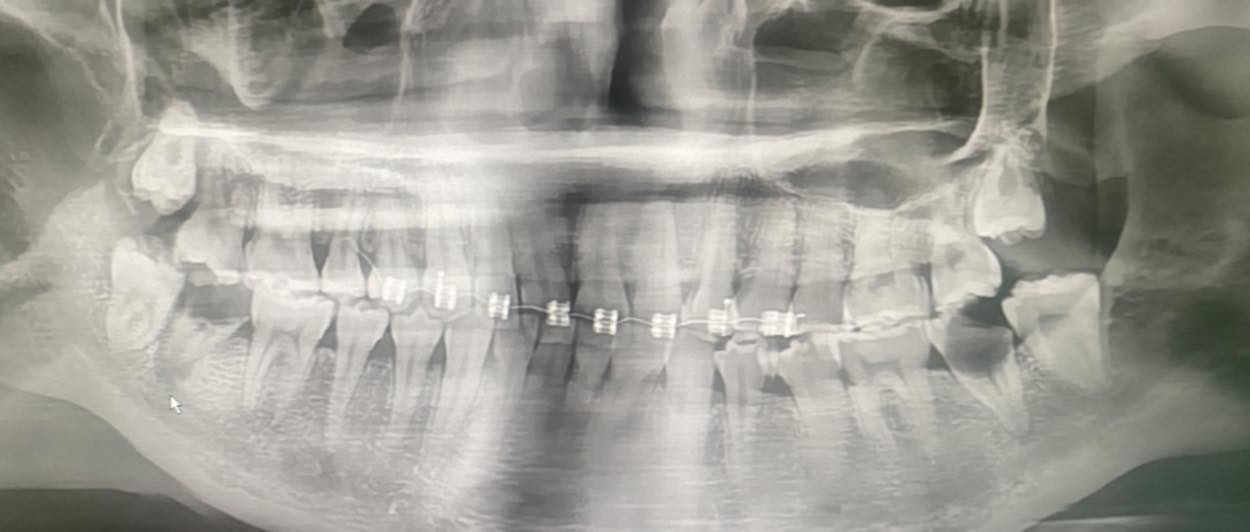

เคสจริงที่หมอเจอ น้องอายุเพียง 20 ปี

เริ่มจากจัดฟันแฟชั่นในกรุงเทพฯ → ฟันผุ มีหนอง→ เชื้อเข้ากระแสเลือด → จับเชื้อ Streptococcus gordonii→ กลายเป็น เยื่อบุหัวใจติดเชื้อ (Infective Endocarditis)

สุดท้ายลิ้นหัวใจรั่ว ต้อง ผ่าตัดเปลี่ยนลิ้นหัวใจ ทั้งที่ยังอายุน้อยมาก ทั้งหมดนี้ เริ่มต้นแค่เพราะ “อยากจัดฟันแฟชั่น”

จัดฟันแฟชั่นทำมาจาก กทม. สัก 6 เดือนที่แล้ว ไอ หายใจไม่ค่อยสะดวก โทรหาแม่ แม่เลยพามารักษาที่น่าน อายุ 20 ปี แม่ให้ลาออกจากงานมารักษาตัวให้หายก่อน

จัดฟันแฟชั่น เป็นหมู่คณะพร้อมเพื่อนอีกหลายคน โอย โอย เพื่อนรู้ยัง บอกแล้ว ก็แล้วแต่พวกมันละกันหมอ

เหมือนไม่มีอะไร เหมือนไม่รุนแรง แต่อีกช่วงชีวิตหนึ่ง ที่ต้องใช้ลิ้นหัวใจเทียมไปตลอดชีวิตคิดให้ดีดีกับการจัดฟันที่ไม่ได้มาตรฐาน ตระหนัก และ ตระหนก กันด้วยนะคะ